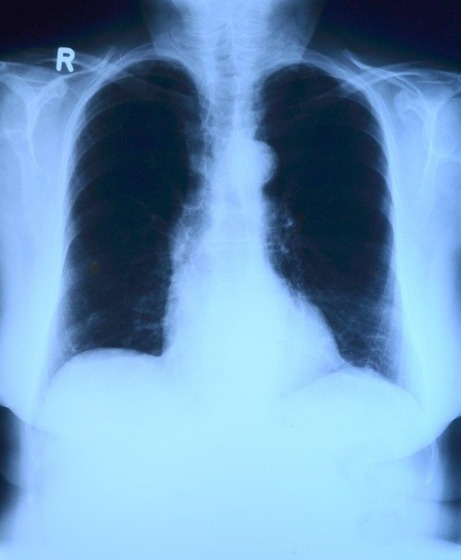

上半身のレントゲン写真

toubibe

むちうちで腰痛の症状が出た時は、まずは整形外科を受診してください。

整形外科では、医師が治療を行い、レントゲンやMRIなどの機器が使用され、精密検査を受けることができます。

また、検査の結果によって必要な場合は、手術を受けることも可能です。そして、症状の程度に合わせて湿布や痛み止めの処方も行われます。

そして、整形外科を受診した際は、医師に診断書を作成してもらいましょう。診断書は、ケガと交通事故との因果関係を明らかにしたり、損害賠償請求のときに必要になる重要な書類です。そのため、交通事故にあった場合は、まずは整形外科を受診しましょう。